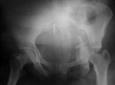

Kalça kırığı, genellikle yaşlı bireylerde görülen ve düşme gibi travmatik olaylar sonucunda meydana gelen ciddi bir yaralanmadır. Bu yaralanma, femur başı veya femur boynu gibi kalça bölgesindeki kemiklerin kırılmasıyla karakterizedir. Kalça kırıkları, hareket kabiliyetini kısıtlayarak yaşam kalitesini önemli ölçüde etkileyebilir. Bu makalede, kalça kırığının belirtileri, tanı yöntemleri ve tedavi yöntemleri üzerinde durulacaktır. Kalça Kırığının BelirtileriKalça kırığı belirtileri, yaralanmanın ciddiyetine ve bireyin genel sağlık durumuna bağlı olarak değişiklik gösterebilir. Genellikle aşağıdaki belirtiler gözlemlenebilir:

Bu yöntemler, kalça kırığının tam yerini ve türünü belirlemek için kritik öneme sahiptir. Tedavi YöntemleriKalça kırığının tedavisi, kırığın tipi, hastanın yaşı ve genel sağlık durumu gibi faktörlere bağlı olarak değişiklik gösterir. Genel olarak kullanılan tedavi yöntemleri şunlardır: